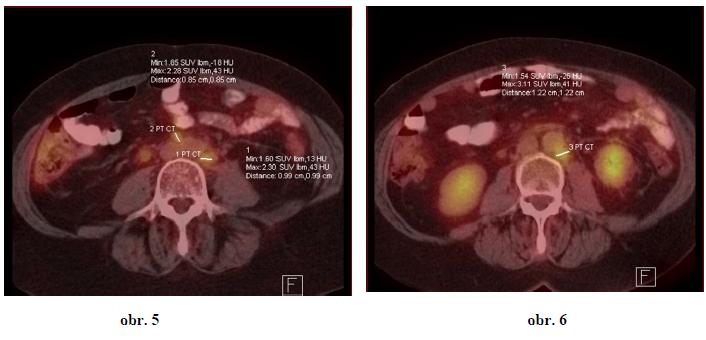

Druhá pacientka ZR r. 1956, dg. 2002 ca mammae l.dx T1 N1 M0, pT1c pN1 pM0, histol.: infiltrující lobulární ca, ER 50%, PR30%, HER2neu 2+, FISH nebyla nalezena amplifikace, mutace BRCA1,2 nebyla vyšetřena.

Adjuvantní léčba byla ukončena 6/2010 (v prodloužené hormonální adjuvanci).

1. generalizace PET/CT 8. 8. 2012 – vícečetná ložiska nacházíme ve skeletu, v LU retreperitonea + ascites malé pánve (obr.5,6)

9. 10. 2012 – zahájena léčba weekly paklitaxel 80mg/m2 + Avastin 10mg/kg á 14 dní

26. 7. 2013 PET/CT - ložiska hypermetabolismus glukózy svědčící pro viabilní neoplasii dnes nenacházíme – CR (obr. 6, 7)

Závěr 2

Pacientka je od 26. 7. 2013 v kompletní v remisi (CR). Léčba Paklitaxelem ukončena, pokračuje pouze léčba monoterapií Avastinem 10 mg/kg á 14 dní. Další kontrolní PET/CT bude provedeno v listopadu 2013.